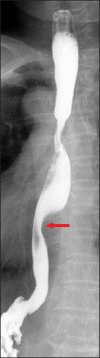

Dysphagia aortica is a rare etiology of dysphagia resulting from extrinsic compression of esophagus by thoracic aortic aneurysm or tortuosity and elongation of thoracic aorta. The clinical findings resemble those of esophageal malignancy or esophageal motility disorders. Therefore, primary diagnosis of dysphagia aortica is very difficult. We, herein, report a case of dysphagia aortica aggravated by wearing the abdominal binder in a 70-year-old woman and review the literature pertaining to this condition. Dysphagia aortica should be considered in the differential diagnosis of dysphagia.